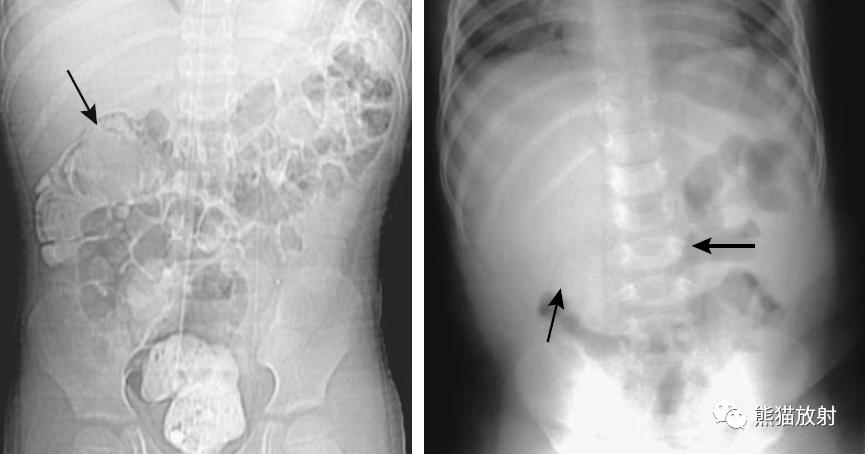

盲肠肠扭转。 盲肠明显扩张并移位至左侧(箭头)。右腹部可见小肠扩张,提示继发小肠梗阻。

盲肠扭转。X线摄片显示中腹部肠管明显扩张(箭头)。钡餐检查示升结肠扭曲部位可见特征性的鸟嘴征(箭头)。